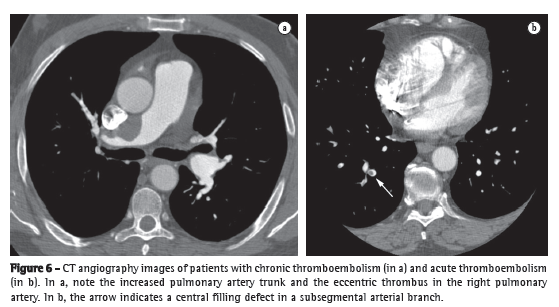

Having been widely studied, CT angiography has gained significant ground in the evaluation of acute PTE, becoming as accurate as pulmonary angiography but without its invasive nature. Some authors consider CT angiography to be the diagnostic imaging method of choice in the assessment of acute PTE.(34-36) This is explained by the various advantages of CT angiography: its high resolution allows the visualization of arteries and filling defects up to the distal portion of the pulmonary vasculature, reaching subsegmental vessels of 2-3 mm (Figure 6); it has excellent interobserver agreement, far superior to that of scintigraphy; its sensitivity is so high that a negative test result allows the safe discontinuation of anticoagulation therapy.(37) One must be alert, however, to the dangers inherent in the method. Technical or pathophysiological factors might lead to the interpretation of pseudo-filling defects, providing false-positive results. The possibility of motion artifacts in patients with tachypnea should be taken into consideration, as should the time interval between contrast injection and image acquisition, as well as the occurrence of hypoxic pulmonary vasoconstriction in poorly aerated regions. The advent of 64-channel scanners created another danger: the possibility of an excessive number of false-positive results. However, that possibility was ruled out in a recent study.(38)